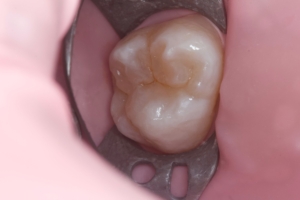

Сучасні композиційні матеріали для реставрацій ідеально відновлюють естетику зубного ряду. Лікар підбирає прозорість та відтінок матеріалу аби пролікований зуб не відрізнявся від сусідніх здорових.

Вид матеріалів підбирає лікар залежно від конкретного випадку, виду карієсу, локалізації ураження.

Приклади робіт лікаря-стоматолога

Естетична реставрація. До / після